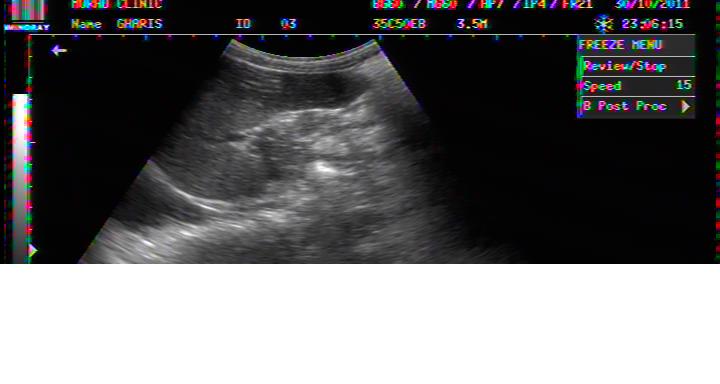

FLUID AROUND LIVER IN DHF

PLASMA FLUID AROUND LIVER IN DHF